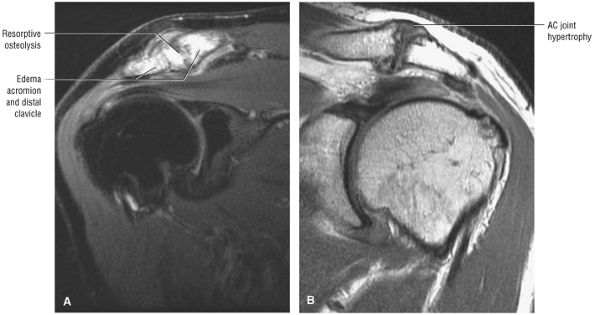

-

The AC joint may hypertrophy, but it is not responsible for true impingement.

The imaging reference to hypertrophy of the coracoacromial ligament correlates with fraying or fragmentation of the ligament in association with impingement.